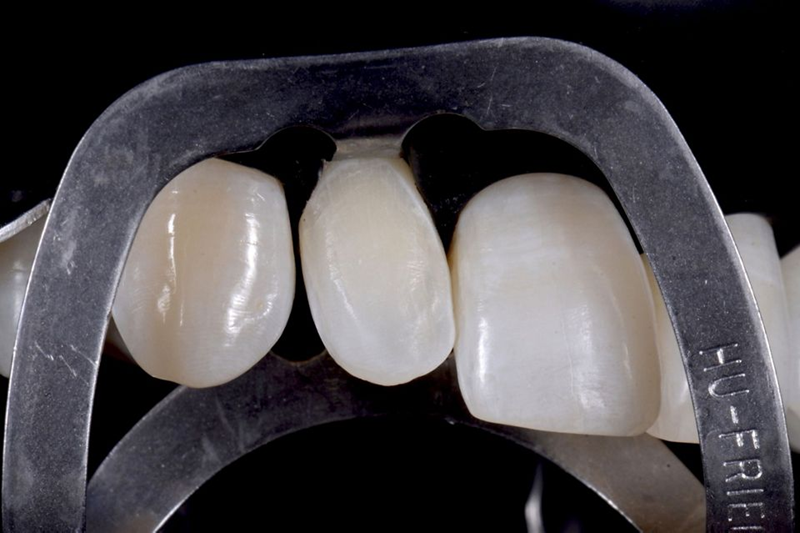

然后,对前庭侧陶瓷铣削后待贴面的氧化锆牙冠进行造型。一旦完成此步骤,就以此为参考生产氧化锆牙冠(图51)。铣削氧化锆牙冠和陶瓷贴面后,使用复合水泥将牙冠固定在 Variobase® 上(图 52)。然后,对最终的牙冠进行仔细抛光并调整以适应患者口腔中的位置(图53-54)。

Fig. 52: After the milling of the zirconia crown and its ceramic veneering, the crown was fixed on the Variobase® by...

Fig. 53: Vestibular view of the final crown.

Fig. 54: Palatal view of the final crown.